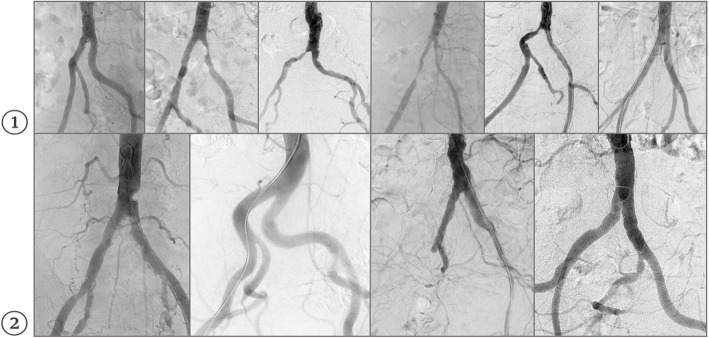

Background: This retrospective study evaluates the diagnostic performance of an optimized comprehensive multi-stage framework based on the Segment Anything Model (SAM), which we named Dr-SAM, for detecting and grading vascular stenosis in the abdominal aorta and iliac arteries using digital subtraction angiography (DSA).

Materials and methods: A total of 100 DSA examinations were conducted on 100 patients. The infrarenal abdominal aorta (AAI), common iliac arteries (CIA), and external iliac arteries (EIA) were independently evaluated by two experienced radiologists using a standardized 5-point grading scale. Dr-SAM analyzed the same DSA images, and its assessments were compared with the average stenosis grading provided by the radiologists. Diagnostic accuracy was evaluated using Cohen's kappa, specificity, sensitivity, and Wilcoxon signed-rank tests.